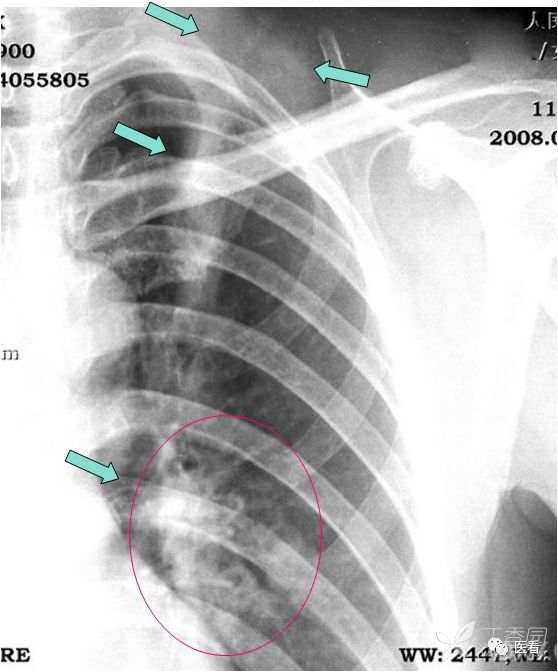

本例因为躁动明显,产生的伪影显著、杂乱。

女,40岁。咳嗽、发热3天。体温38.7℃。

此病例初诊报告描述了左上肺野和肺门阴影,考虑炎性病变。建议进一步检查。报告医师起初考虑肺炎,结核待除外。

辨识:1.阴影向上出了肺野,与软组织相连,向下直达肺门(箭示);2.肺门处多发环状影太规整,不支持钙化淋巴结(红圈)。

看了病人,原来是少见的铁梅式的独辫,又粗又大。肺门结节影为扎头绳带着扣状塑料结(红圈区)。